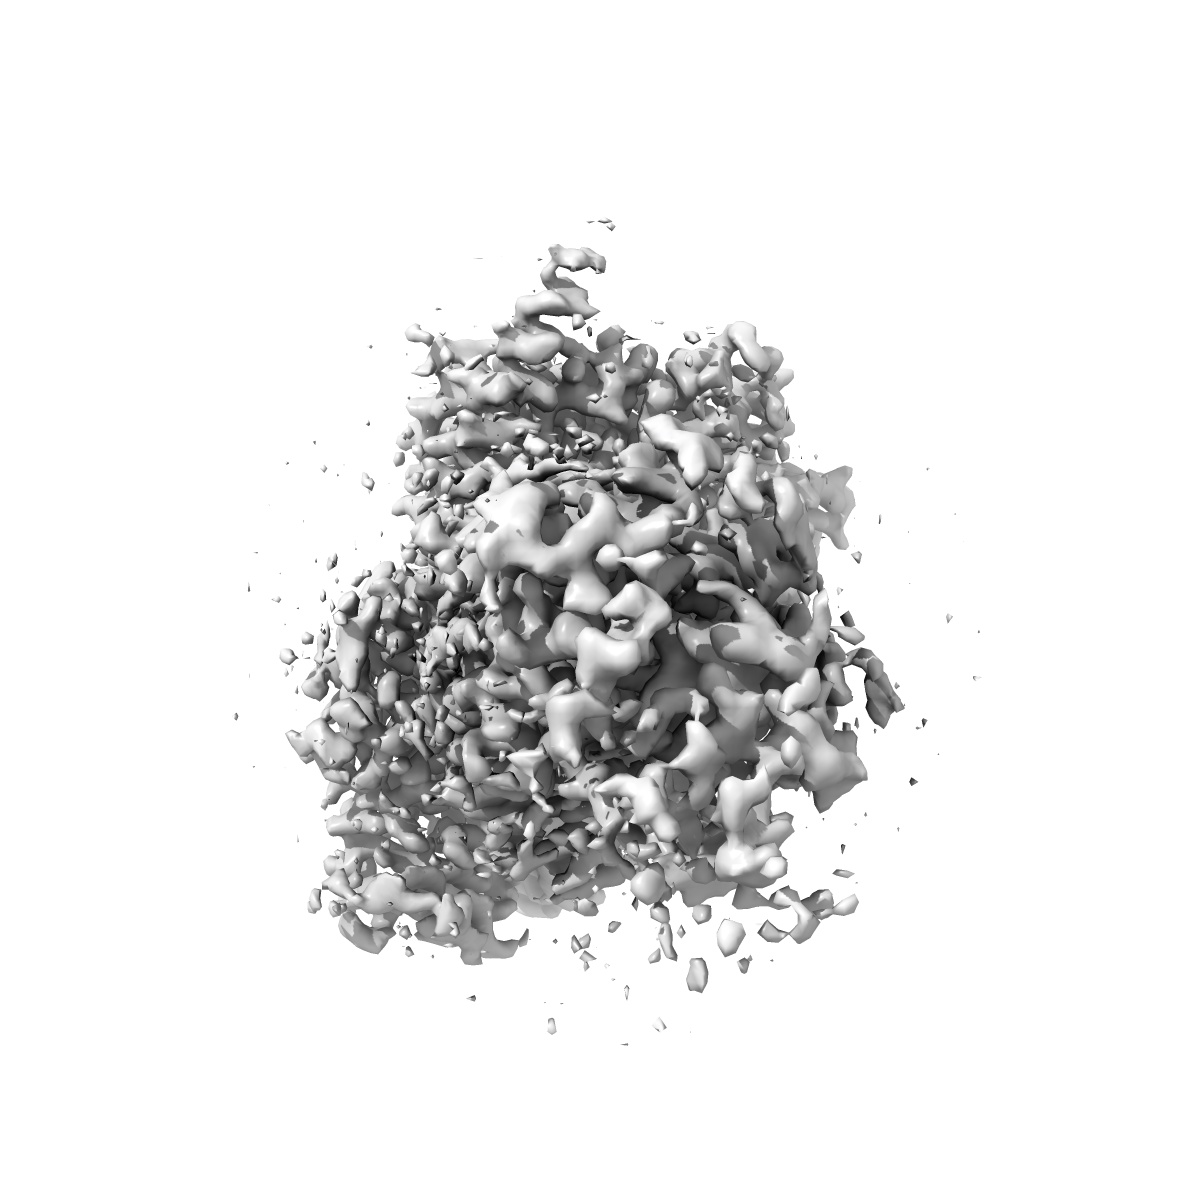

Human calcitonin Receptor in complex with Gs and cagrilintide in the CT-like conformation

Single-particle2.5 Å

Sample: Human calcitonin Receptor in complex with Gs and cagrilintide in the CT-like conformation

Structural and dynamic features of cagrilintide binding to calcitonin and amylin receptors.

(2025) Nat Commun , 16 , 3389 - 3389